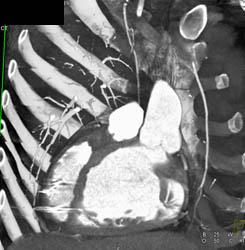

Diagnosis

Normal RCA